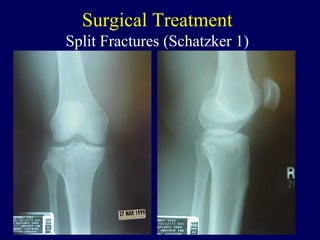

Surgical Treatment

Split Fractures (Schatzker 1)